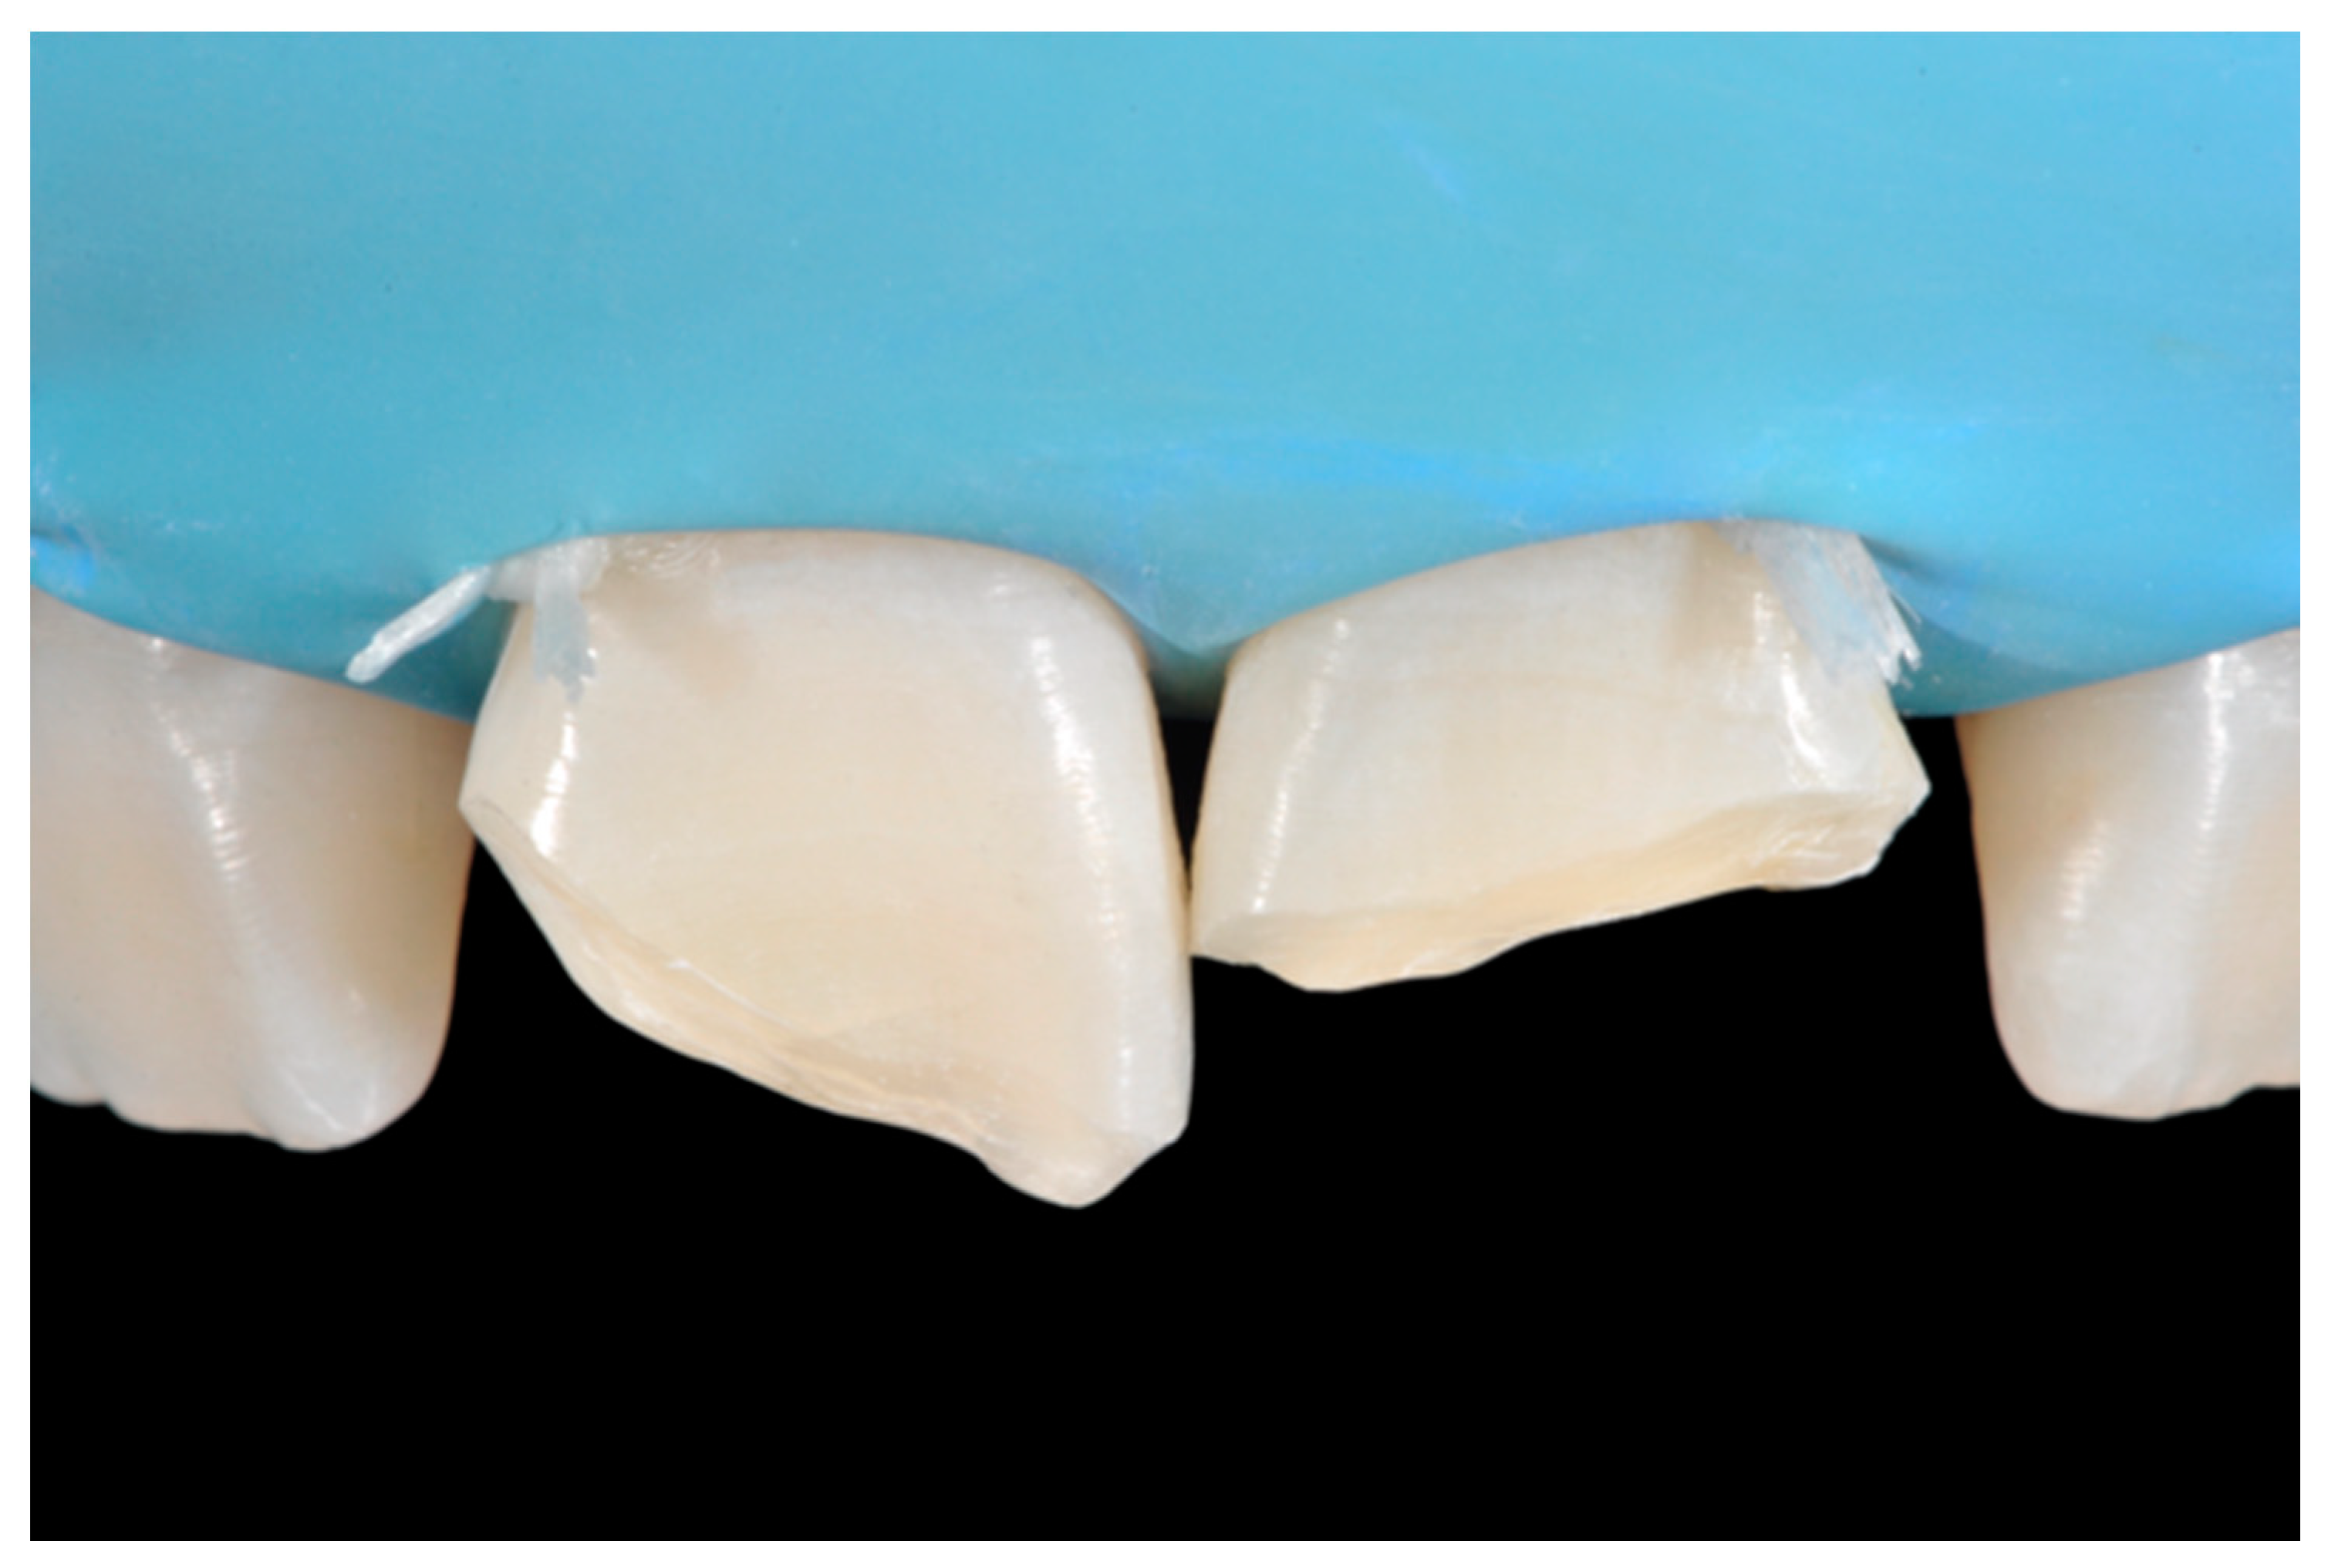

Once completed, the two frames (Clearfil Majesty ES-2, A1E, A2D, Kuraray Noritake Dental, Tokyo, Japan) showed internal and external excesses that were reduced using diamond burs and discs (Figure 33 and Figure 34) strictly following the procedure described in Section 2.1.2 of present article. Excesses were removed from the distal-incisal angle of #2.1 allowing therefore to obtain the desired translucency. After silane application and bonding procedure (Figure 35) as described in Section 2.1.2, restorations were completed (Figure 36 and Figure 37). They both show satisfactory clinical integration 1.5 years post-operative (Figure 38 and Figure 39).

Figure 34.

Frame is also trimmed reducing external outline. Reprinted from Restauri diretti nei settori anteriori, G. Paolone, S. Scolavino, © 2021, with permission from Quintessence Publishing Italy.

Figure 35.

The modified frames treated with silane coupling agent and adhesive, ready for layering of dentinal body. Reprinted from Restauri diretti nei settori anteriori, G. Paolone, S. Scolavino, © 2021, with permission from Quintessence Publishing Italy.